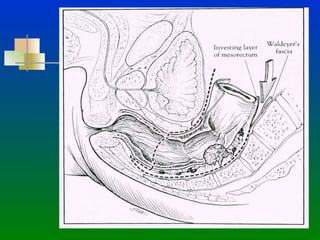

CANCER DE RECTO PRESERVACION DE ESFINTER ANATOMIA: El Recto  se divide en 3 tercios: 1/3 Superior :  Se extiende del promontorio del Sacro  hasta la reflexión  peritoneal. 1/3 Medio:  Inicia en la Reflexión Peritoneal anterior hasta  5-6 cms. del margen anal. (10-11 cms del margen anal) 1/3 Inferior : Inicia a los 5-6 cms. del margen anal y termina  en el esfínter anal.

CANCER DE RECTOPRESERVACION DE ESFINTER ANATOMIA: El Recto se divide en 3 tercios: 1/3 Superior : Se extiende del promontorio del Sacro hasta la reflexión peritoneal. 1/3 Medio: Inicia en la Reflexión Peritoneal anterior hasta 5-6 cms. del margen anal. (10-11 cms del margen anal) 1/3 Inferior : Inicia a los 5-6 cms. del margen anal y termina en el esfínter anal.